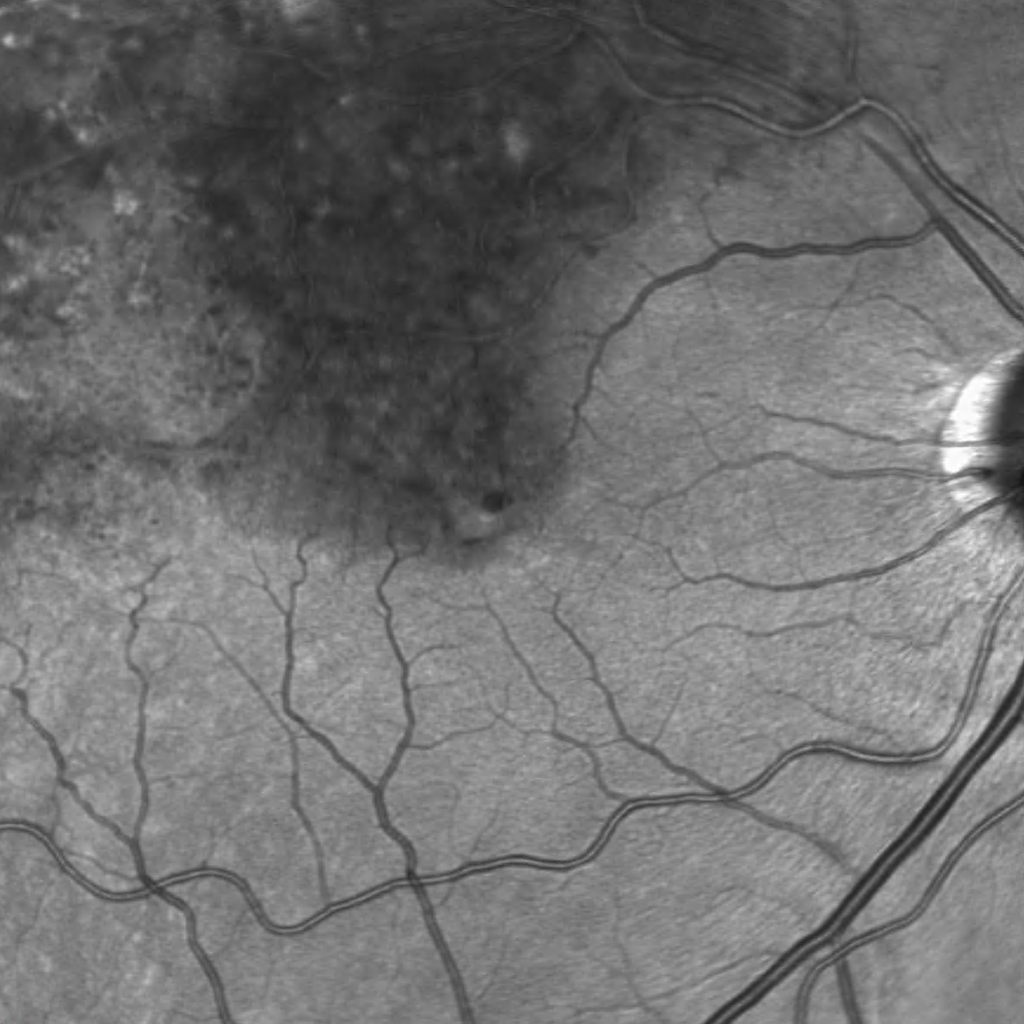

In dry AMD, these degraded products cannot be removed sufficiently, leading to a gradual build-up of waste products, so-called drusen, beneath the RPE cell layer. If the number and size of the drusen increase significantly over time, some RPE cells become damaged and may die. The photoreceptor cells above can no longer be adequately supplied with nutrients and can also die, leading to vision loss in this area. In its late stage, dry AMD is referred to as Geographic Atrophy.

The image illustrates changes in the macula such as cystoid changes and drusen.